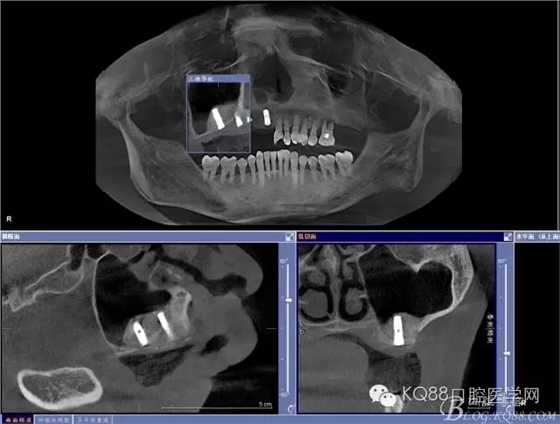

輔助檢查:ct示骨密度良好,11 12區(qū)域骨下有一水平向埋伏牙,15 16區(qū)域骨高度2.5-3mm,骨寬度6-9mm。

治療計劃:11 12 13及埋伏牙拔除,同期上頜竇外提升手術(shù)及種植修復(fù)

定位桿定位,擴孔,備洞,bio-oss骨粉和CGF混合后充填竇腔

植入植體,骨島覆蓋上頜骨側(cè)壁骨窗